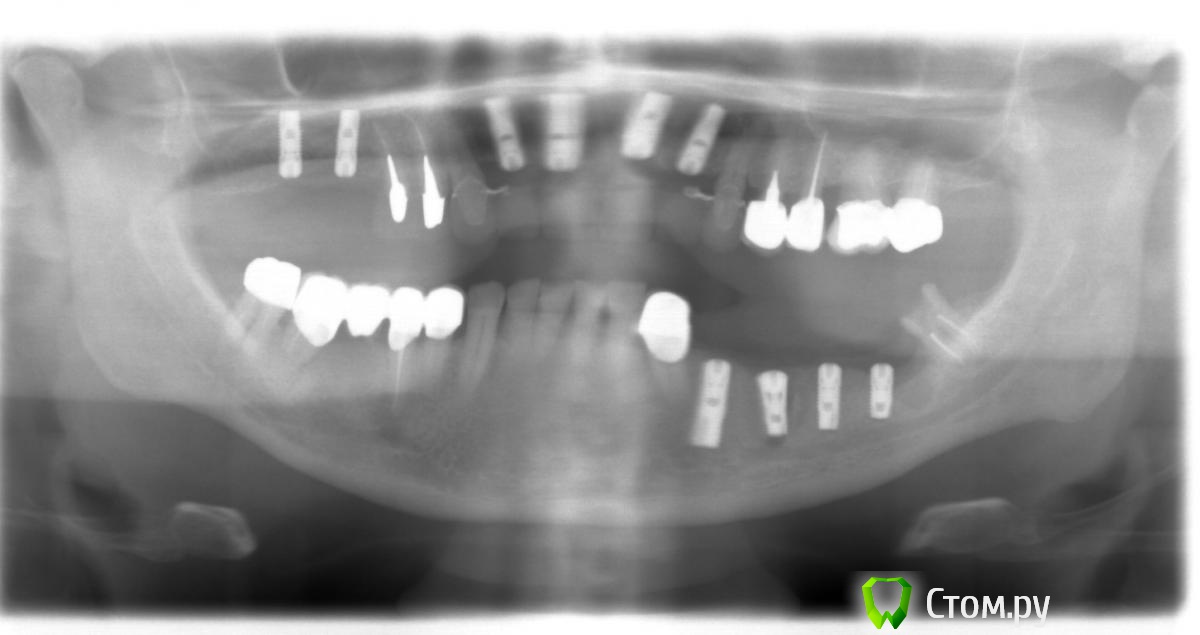

Doc Опубликовано 5 мая, 2014 Поделиться Опубликовано 5 мая, 2014 2004 год, первое посещение. 2004 год, первые имплантаты 2009 год, добавили два имплантата в область 26-27, которые по просьбе пациента были оставлены "без гарантии, пока сами не запросятся наружу", что и случилось через пять лет. Пациент претензий не имел. Сегодня утром, 5 мая 2014 года: По мне так для пациента возраста 68 лет через десять лет упорного жевания картина из серии "дай Бог каждому!". 8 Ссылка на комментарий